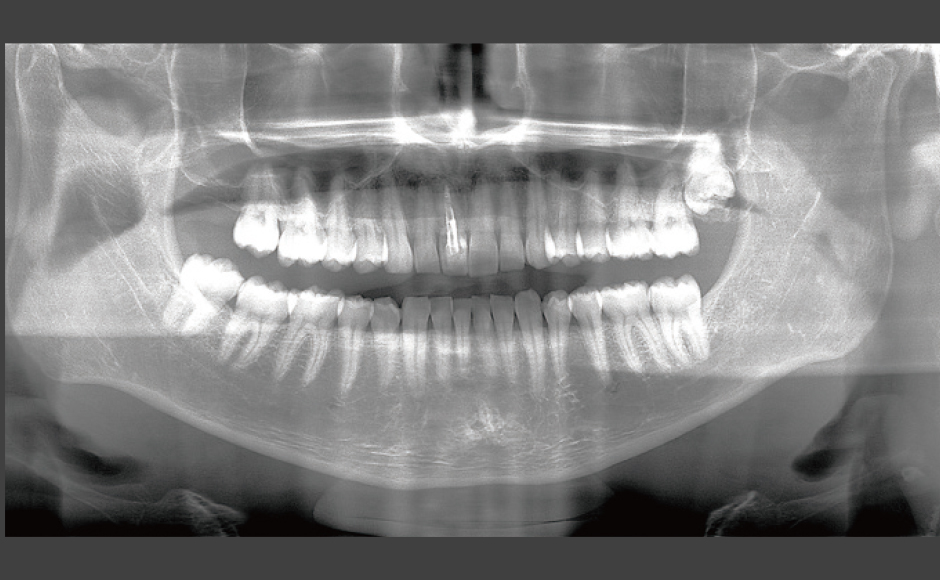

Astratech Implant System EVを使用した審美領域のインプラント治療

症例1:Socket Shield Technique(SST)を用いた審美領域のインプラント治療

症例2:硬軟組織のグラフトを施した審美領域のインプラント治療